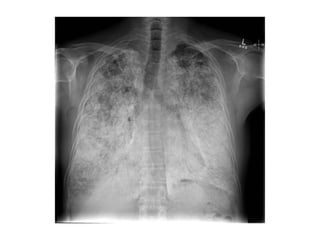

-Features on chest radiographs include ground-glass

opacification, small nodular opacities, “shaggy” cardiac

silhouette, and ill-defined diaphragmatic contours, it has

been reported that 80% of patients with asbestosis have

coexistent pleural disease at chest radiography, fibrous

bands are sometimes seen to radiate inward from the

pleura

(a) PA radiograph of a patient with asbestosis shows “shaggy”

mediastinal and diaphragmatic contours, (b) Localized view of the

lung bases of the same patient further illustrates the diffuse

interstitial opacification

PA radiograph shows diffuse fine nodular and reticular opacification

with irregularity of mediastinal and diaphragmatic contours, the

costophrenic angles are blunted because of pleural thickening

PA radiograph of an asbestos-exposed person shows parenchymal

bands radiating in from the pleura in both mid zones (arrows),

diffuse pleural thickening is predominantly left-sided